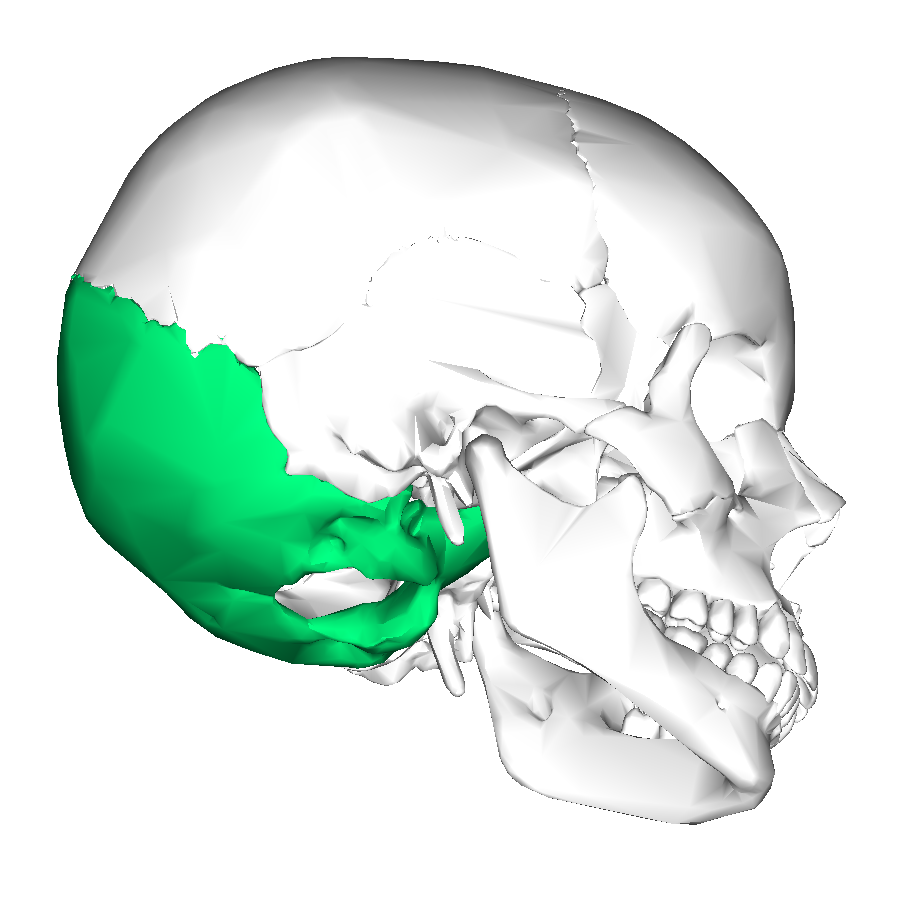

What is this region?

Occipital Bone